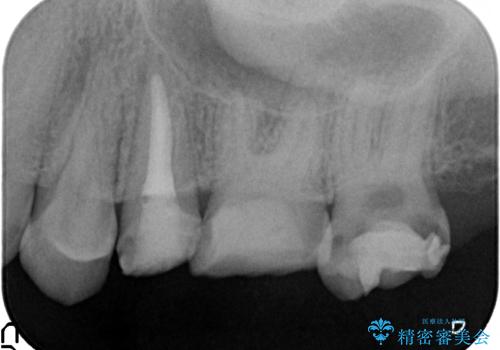

- 左上の歯が痛くてものが咬めないといらっしゃった方の症例です。

左上6は自発痛および持続痛を認めたため根管治療後、オールセラミッククラウンによる補綴を行いました。

左上7は冷水痛のみだったため、慎重に虫歯の除去を行い症状がないことを確認後、オールセラミッククラウンによる補綴を行いました。

左上5は再根管治療後、オールセラミッククラウンによる補綴を行いました。